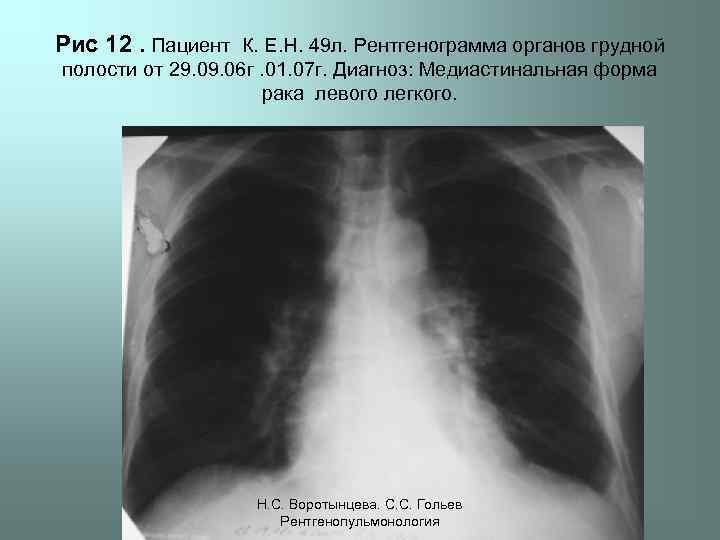

Рис 12. Пациент К. Е. Н. 49 л. Рентгенограмма органов грудной полости от 29. 06 г. 01. 07 г. Диагноз: Медиастинальная форма рака левого легкого. Н. С. Воротынцева. С. С. Гольев Рентгенопульмонология